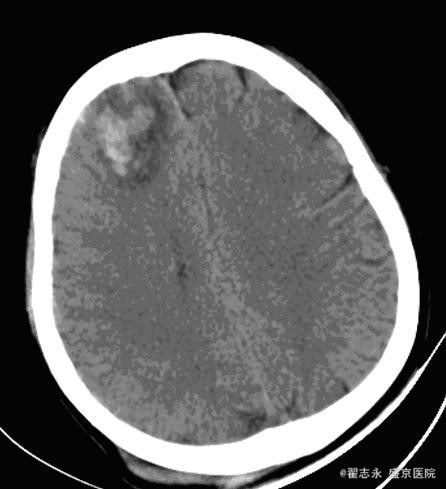

肝炎后肝硬化失代偿期并发脑出血

患者女,55岁。丙肝后肝硬化,全血细胞减少,白细胞计数,2.7*10^9/L,血红蛋白,54g/L,血小板计数,5*10^9/L。突然出现头痛。

2小时后突然意识不清,考虑再出血。后死亡。

脑内出血的可能病因有高血压、动脉瘤、动脉硬化、脑动脉淀粉样变性、动静脉畸形、血液病等。 肝炎后肝硬化失代偿期并发脑出血, 临床症状多不典型, 如果不及时进行仔细检查, 易误诊为肝性脑病或电解质紊乱。肝硬化失代偿期并发脑出血, 发病前无前驱症, 病情进展迅速, 突然发生意识障碍, 出血量大, 病情危重, 病死率高。 发病机制, 可能与下列因素有关: 1、肝炎后肝硬化失代偿期肝功能贮备能力下降, 维生素K 吸收差, 凝血因子和凝血酶原合成障碍, 导致凝血功能下降。2、肝炎后肝硬化失代偿期大多数有脾功能亢进, 继发性血小板减少。3、肝炎后肝硬化失代偿期继发性醛固酮增高, 出现高醛固酮血症, 导致水、钠储留, 器官血流量增加, 内脏血管及全身血管扩张, 处于高动力循环状态, 血管承受的压力大, 易导致脑血管破裂。4、毛细血管脆性增加。 血液病所致脑出血,多位于脑皮层,可能为多处。且血肿不均匀。在血液病未纠正情况下,极容易再出血,再出血量大,死亡率高。